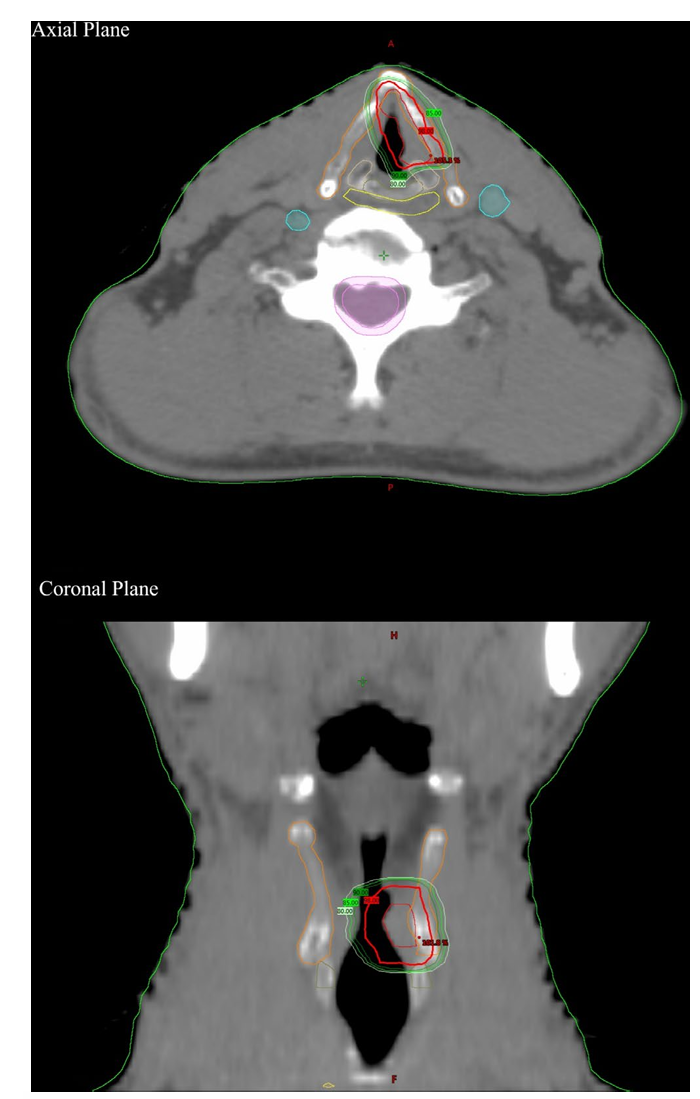

本研究为一项单中心回顾性分析,旨在评估超低分割放疗在早期声门癌患者中的临床应用效果。研究共纳入2017年6月至2021年1月期间诊断为早期声门鳞状细胞癌的22例患者,所有患者均因全身状况不佳、麻醉禁忌或无法定期往返医院等原因无法接受常规手术或放疗。患者肿瘤分期包括Tis、T1a和T2期,其中15例患者存在前联合受累。所有患者均接受了针对受累声带的超低分割放疗,总剂量范围为35至42.5 Gy,分5次完成,具体剂量根据肿瘤体积和患者情况个体化调整。在治疗计划设计中,临床靶体积主要包括病变声带及其周边关键结构,如后部声带肿瘤时包括同侧杓状软骨的一半,前部肿瘤时包括前联合,若前联合受累则包括对侧声带前2毫米区域。计划靶体积在各方向上采用各向异性外扩,头脚方向为5毫米,左右及前后方向为3毫米。放疗技术以容积调强弧形治疗为主,部分患者采用调强放疗,所有治疗均在直线加速器上实施,每次治疗前均进行锥形束CT图像引导以确保定位精度。

图1:等剂量曲线和结构